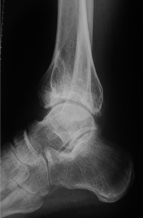

X片:检查可以显示关节间隙狭窄、骨赘形成、软骨下骨硬化等特征性表现;

目前应用最广的是踝关节骨关节炎分期为Takakura-Tanaka分期:

0期:踝关节平行,无关节炎征象;

Ⅰ期:踝关节平行,无关节间隙狭窄,有早期软骨下骨硬化或骨赘形成;

Ⅱ期踝内侧关节间隙狭窄,无软骨下骨接触;

Ⅲ期又可分Ⅲa期和Ⅲb期:

Ⅲa期 踝内侧间隙消失,软骨下骨接触面局限于内侧;

Ⅲb期 踝软骨下骨接触延伸至距骨穹窿部;

Ⅳ期 踝关节间隙消失伴全部软骨下骨接触。